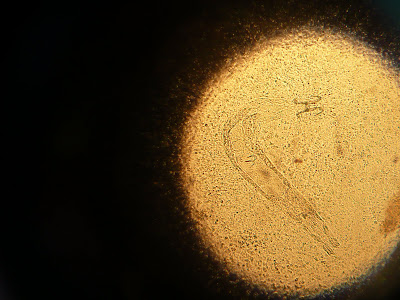

Het werd al vrij snel duidelijk wat er loos was, zie onderstaande videos:

De parasieten huidworm, kieuwworm, costia, chilodonella en zelfs trichodina werden op deze Kohaku gevonden. Daarnaast is de gatenziekte aanwezig, welke voornamelijk door de Aeromonas of Pseudomonas-bacterie wordt veroorzaakt.

De huidworm (Gyrodactylus) en kieuwworm (Dactylogyrus), te onderscheiden doordat de kiewworm eierleggend is en de huidworm levendbarend is. Daarnaast is de kieuwworm over het algemeen kleiner dan de huidworm en toont de kieuwworm twee paar donkere oogvlekken, welke duidelijk zichtbaar zijn. In één huidworm kan onder een microscoop wel drie tot vier generaties zichtbaar zijn, waarbij de nakomelingen zich al aan het ontwikkelen zijn binnen in het lichaam.

De Gyrodactylus is hemafrodiet (tweeslachtig) en kan zichzelf voortplanten. Deze worm voedt zich met bloed en epitheelresten van zijn gastheer.